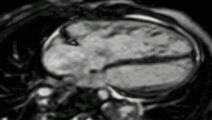

بطن راست بزرگ شده با عملکرد ضعیف در بیمار با ترتالوژی ترمیم شده از Fallot توسط CMR